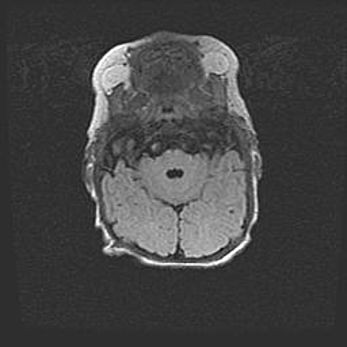

Подострая гематома правой гемисферы мозжечка.

Наружная гидроцефалия.

Возраст: 15 дней

Вес: 3100 г

Пол: женский

Окружность головы: 37 см

Срок гестации: 35-36 недель

При открытой наружной форме гидроцефалии у новорожденных расширяются и переполняются субарахноидные пространства.

Кровоизлияния в мозжечок имеют две клинико-анатомические формы: полушарные гематомы и кровоизлияния в червь.

К появлению этой патологии может привести: повреждения головного мозга, возникающие в результате асфиксии и гипоксии плода при беременности, или травмы во время родов. Редко гематома мозжечка может быть результатом первичной коагулопатии и сосудистой мальформации, диссеминированном внутрисосудистом свертывании, изоиммунной тромбоцитопении.